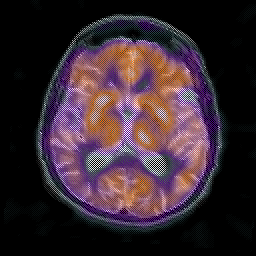

Alzheimer's disease: overlay -- Slice #13

[Home][Help][Clinical] Slice 13